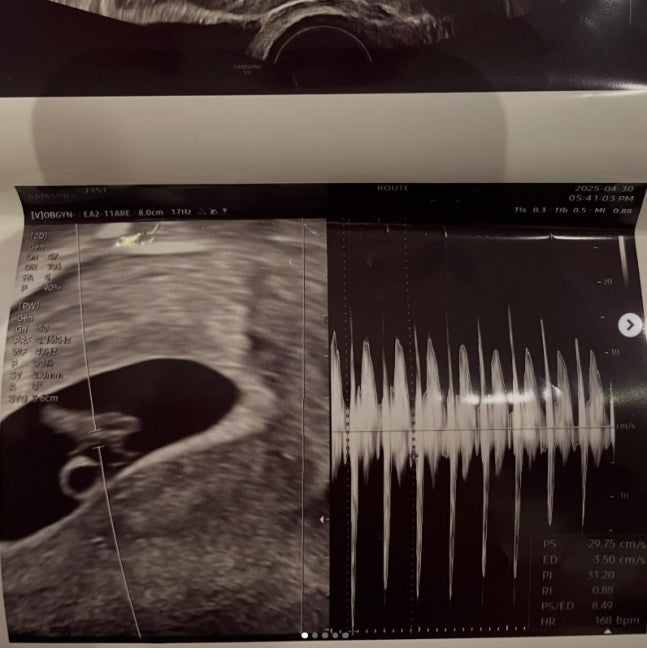

서민재는 하루 전, 개인 SNS에 "아빠된 거 축하해♥"라며 초음파 사진, 남자친구 A씨와 함께 찍은 셀카 여러 장을 게재했다. 서민재는 A씨의 실명도 공개했다. 이어 서민재는 두 개의 게시물을 추가로 업로드, A씨와의 진한 스킨십이 담긴 근황 사진을 대방출했다.